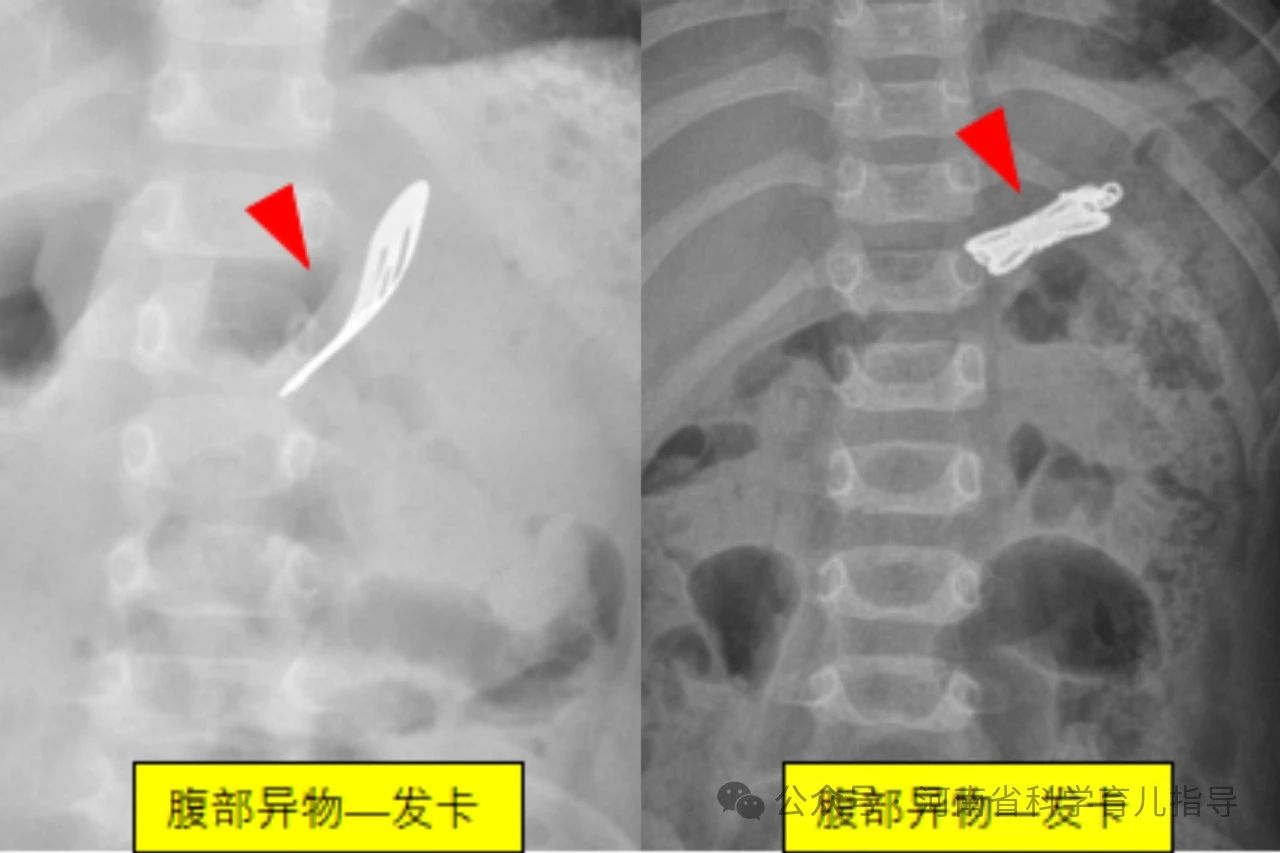

消化道异物儿童消化道异物是指儿童误吞了不能被消化且未及时排出而滞留在消化道的各种物体,文献中已报道的有硬币、果核、碎骨、电池、磁性异物、玩具、指甲、乳牙、笔头、塑料笔帽、电动牙刷头、大头针、戒指、图钉、螺丝钉、别针、纽扣、毛发等等。根据其形状主要包括以下几种,圆钝型异物如硬币,钢珠,螺丝帽,电池,棋子等圆形或者边缘比较平钝、光滑的物体,扁平状或球型。尖锐型异物如针状,钉状或者钩状物体,还有不规则型异物如女性的金属饰品发卡,生活用品如温度计中的水银等。其中形状不规则或者尖锐异物、纽扣电池、多枚磁性异物或单枚磁性异物合并金属异物发生并发症的风险较高,危险性较大。

下面来看一组尖锐型消化道异物,下图。